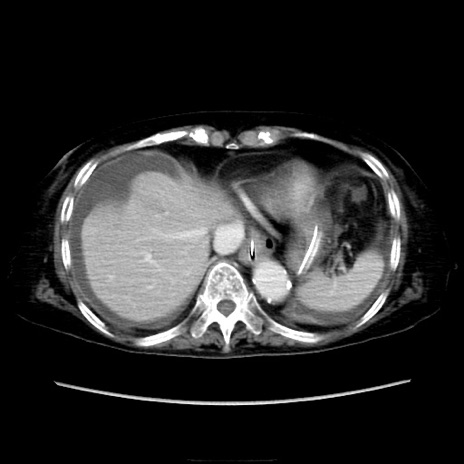

症例40(横断像)

他院CT

横断像